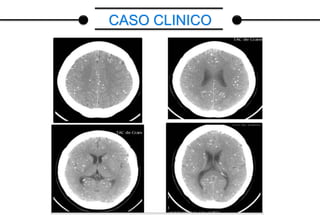

CASO CLINICO

Datos: nombre MG, edad 30 años, procedencia Municipio Mara

Motivo de Consulta: perdida del estado de consciencia, movimientos tónico-clónicos

generalizados, sialorrea.

Enfermedad Actual: paciente femenina de 30 años de edad, quien inicia enfermedad

actual minutos previos a su ingreso caracterizado: por presentar perdida brusca del

estado de consciencia acompañada de convulsiones tónico-clónica generalizadas de

una duración aproximadamente mayor de 5 min sin recuperación del estado de

consciencia concomitantemente la paciente presenta sialorrea y desviación superior de

la mirada, motivo por el cual previa valoración se decide su ingreso.

Cuenta blanca 7000mm3

Hemoglobina 11,60mg/dl

Hematocrito 34,70%

Plaquetas 186.000mm3

Creatinina 0,8mg/dl

Glicemia 92mg/dl

Electrolitos

-Na

-K

-Cl

-Ca

134mEq/L

3,80mEq/L

104mEq/L

8,30mEq/L

PARACLINICOS